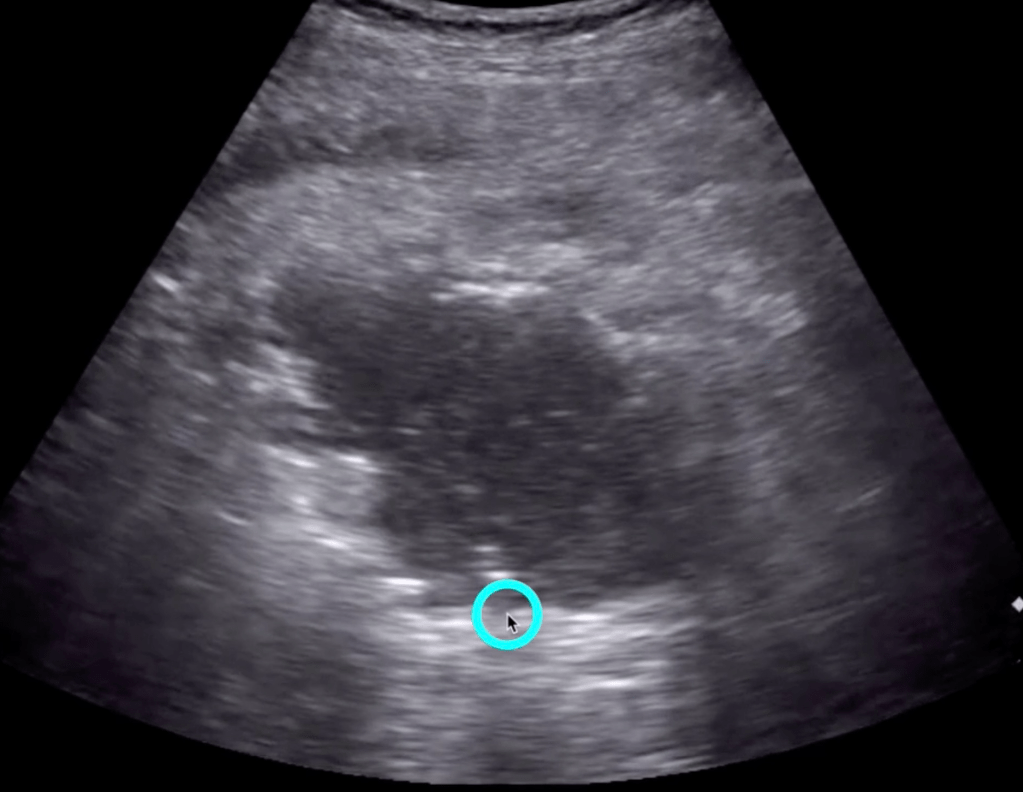

- “Compared with CT, point-of-care ultrasonography had a sensitivity of 92% (95%confidence interval 88% to 96%), specificity of 97% (95% confidence interval 94% to 99%), positive predictive value of 94% (95%confidence interval 90% to 97%), and negative predictive value of 96% (93% to 98%) in the diagnosis of diverticulitis.”

- Check out the new 5 minute Sono Diverticulitis video later in this post

5 Minute Sono

- Large curvilinear probe

- Graded compression up and down

- Diverticula

- Bowel wall>5mm

- Prominent fluid-filled bowel loops

- Pericolic free fluid

- Increased pericolic fat (hyperechoic)

- Abscess